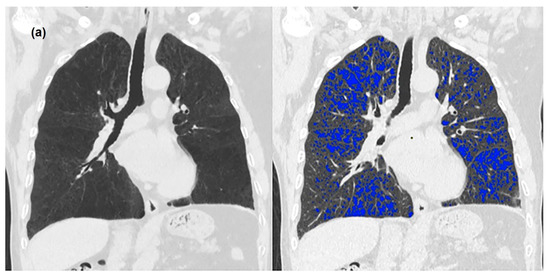

2.3. Image Analysis

3. Results

3.2. Quantitative Measurements of Standard-Dose and Ultra-Low-Dose CT